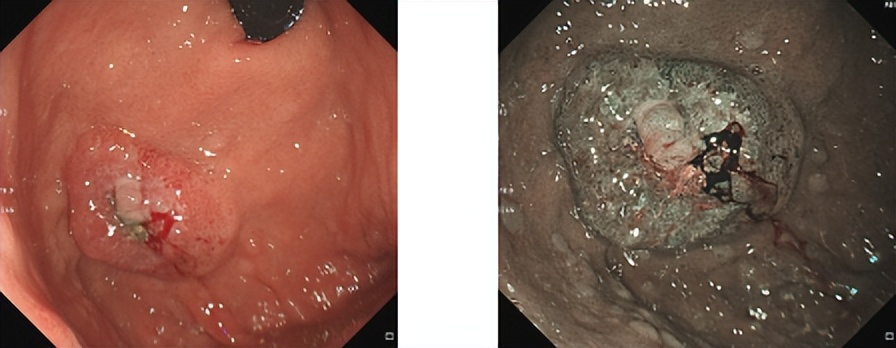

胃镜

胃底近后壁见3*3.5cm大小隆起,宽基底,表面凹凸不平,见糜烂溃疡,质脆,表面结节状充血水肿,有自发性及接触性出血。肠镜检查未见器质性病变。

胃底近后壁活检病理

腺癌,考虑胃原发可能性大。IHC:CK7(+)、Villin(+)、CDX2部分(+)、CK20(-)、GATA-3(-)、ER(-)、HP(-)、P53强弱不等(+)、Ki67约80%(+)。